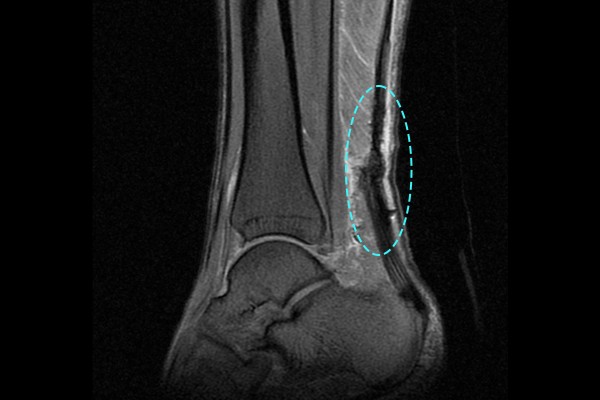

환자분께서는 치료를 위해 의정부 지역 족부전문의를 찾아 검색을 해보시다가 저를 알게되시어 찾아오셨다 말씀하셨습니다. 환자분의 병력을 듣고 나서, 아킬레스 부위를 눌렀을 때 움푹 들어감을 확인하는 딤플 사인(Dimple sign) 양성 소견이 확인 되었고, 정확하게 아킬레스건 상태를 확인하기 위해 MRI 검사를 시행하였습니다.

MRI 검사 결과, 파열된 아킬레스건이 확인되어 좌측 아킬레스건 파열(Achilles rupture ankle Lt.)을 진단하였습니다. 이후 환자분께 현재 아킬레스건 상태와 수술의 필요성을 설명드렸고, 수술적 치료인 아킬레스건 다중봉합술[재건술](Ankle Achilles repair)을 시행하였습니다.